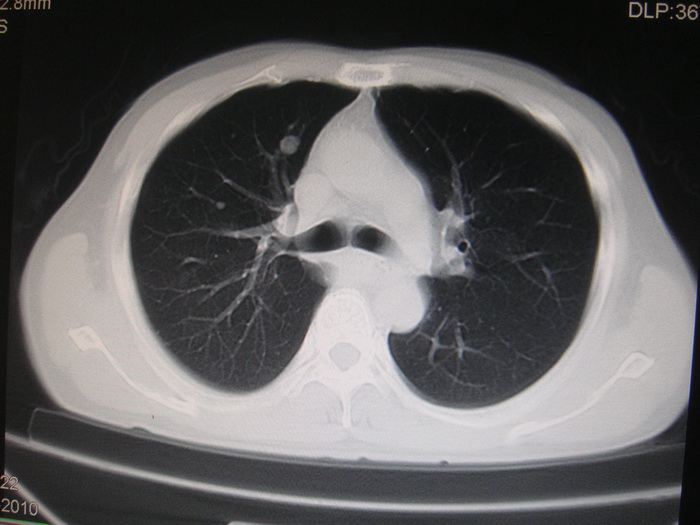

标题: CT28366:男性,45岁,偶尔发现右颈部肿块行胸部CT扫描。 [打印本页]

男性,45岁,偶尔发现右颈部肿块行胸部ct扫描。

两肺多发结节灶及纵膈淋巴结肿大考虑为转移

两肺多发性转移瘤,纵隔淋巴结转移。

两肺多发性转移瘤,纵隔淋巴结转移。食道中上段管壁似乎增厚,作相关检查。

两肺多发性转移瘤,前上纵隔淋巴结转移。